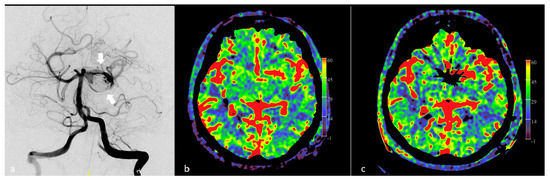

- Yang, M.; Wu, J.; Ma, L.; Pan, L.; Li, J.; Chen, G.; Struffert, T.; Sun, Q.; Beilner, J.; Deuerling-Zheng, Y. The Value of syngo DynaPBV Neuro During Neuro-Interventional Hypotensive Balloon Occlusion Test. Clin. Neuroradiol. 2015, 25, 387–395. [Google Scholar] [CrossRef]

- Ikemura, A.; Yuki, I.; Otani, K.; Ishibashi, T.; Dahmani, C.; Ebara, M.; Abe, Y.; Kajiwara, I.; Watanabe, M.; Murayama, Y. Evaluation of Balloon Test Occlusion Before Therapeutic Carotid Artery Occlusion: Flat Detector Computed Tomography Cerebral Blood Volume Imaging versus Single-Photon Emission Computed Tomography. World Neurosurg. 2019, 133, e522–e528. [Google Scholar] [CrossRef]